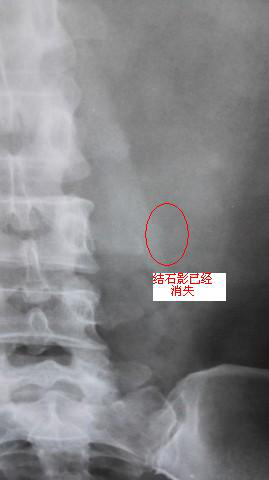

碎石前